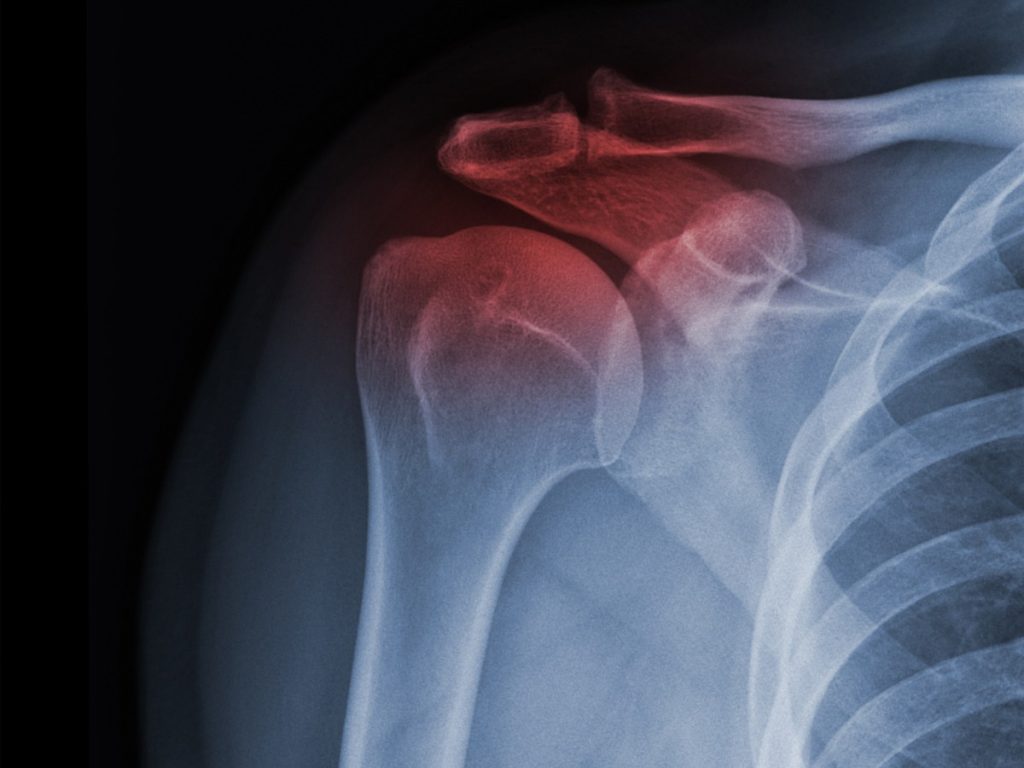

Shoulder Arthritis

Over time, the cartilage that cushions the shoulder joint can wear down, causing aching, stiffness, and limited mobility.

Dr. Mehta offers personalized treatment options, including bracing, regenerative injections, and advanced surgical repair, to reduce the discomfort.